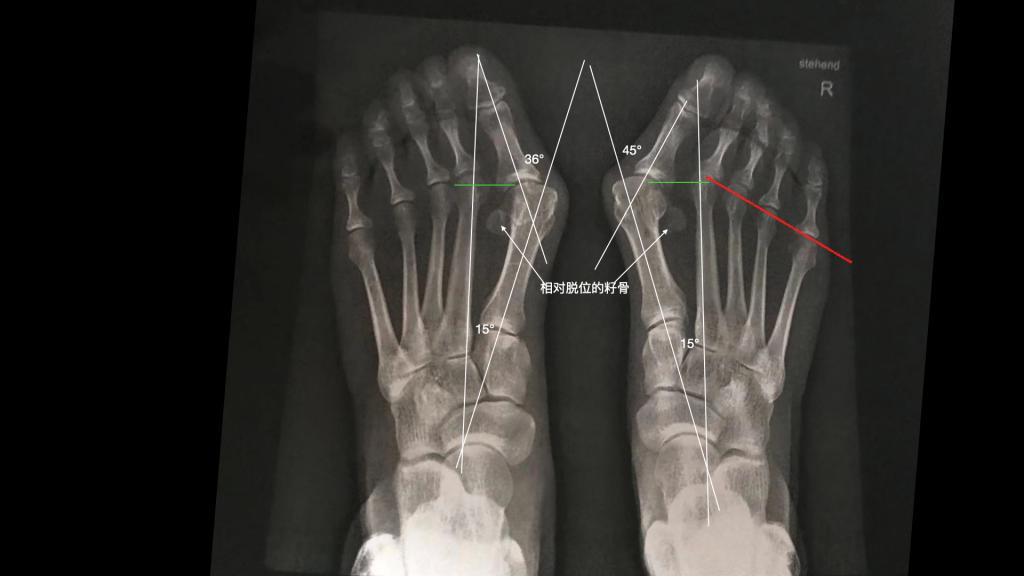

而拇外翻呢,是呈现为以第一跖趾关节变形为主的一种畸形,它是表现为拇外翻角度的增加,主要的是第一二跖骨间的夹角增大,以及第1跖列内收内翻这样的,症状为主的一个疾病一个畸形。踇外翻多见于女性,男性也有相对更加少见。

痛风是典型的,除外全身性的治疗,我们也可以通过手术取出局部痛风石结晶的办法,减少结晶对局部的刺激症状,拇外翻主要以第一跖列的截骨为主,矫正偏斜的第一跖列的骨头,来达成有效矫正拇外翻的效果。